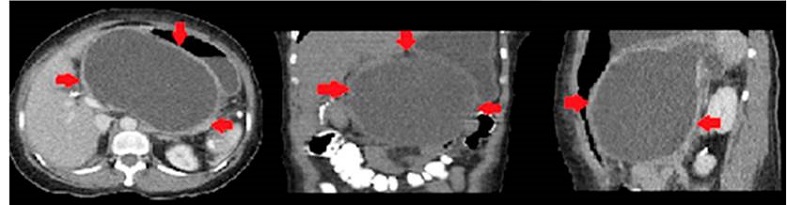

Al examen físico de ingreso en nuestra institución presenta abdomen distendido, dolor y masa palpable en el epigastrio, sin ictericia. Los paraclínicos mostraron hemograma sin leucocitosis, hiponatremia, hipocloremia e hipopotasemia leves, no acidemia metabólica, lactato levemente aumentado e hiperbilirrubinemia leve, a expensas de la directa con amilasemia leve. Se consideró una posible pancreatitis aguda. Ante esta situación se decidió realizar una tomografía computarizada de abdomen contrastado, que reportó pseudoquiste de 1460 mL de volumen aproximado, en contacto con la pared gástrica posterior (Figura 1).